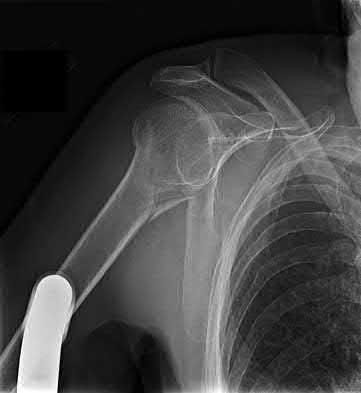

3. # Which of the following is not an appropriate implant for treatment of the fracture seen in Figure A?

1. Cephalomedullary nail

2. External fixation

3. Proximal femoral locking plate

4. 95 degree blade plate

5. Sliding hip screw Corrent answer: 5

The image shows a reverse obliquity intertrochanteric hip fracture.

According to the referenced article by Haidukewych et al, unstable peritrochanteric hip fractures have a worse outcome (failed in 9/16 cases) if treated with a sliding hip screw. Two additional factors that were found to have a strong correlation with postoperative failure (nonunion, loss of reduction) were poor reduction and poor implant placement. In this study, fixed angle devices were superior. Intramedullary fixation has the added advantage of a shorter lever arm and less potential for fracture collapse and limb shortening.

The IMN also acts as a medial buttress.

According to Sanders et al, the dynamic condylar screw (DCS) can also be used in subtrochanteric models, but should not be used if extensive comminution is seen, as they reported a high failure rate with DCS in these fractures if highly comminuted. They report a 77% overall union rate with this device.